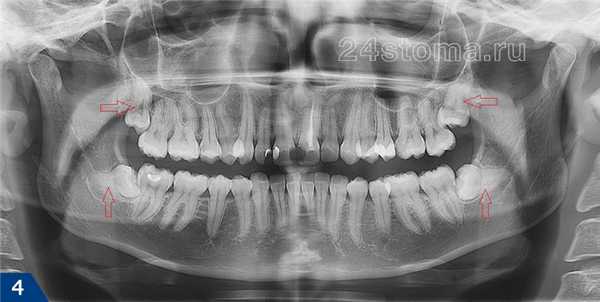

Поэтому четкими будут только однокорневые, а также двухкорневые зубы верхней и нижней челюсти (два корня находятся в одной плоскости) – и причем только на цифровых снимках. А вот передние зубы обоих челюстей на обычных пленочных ортопантомографах будут всегда сильно размыты (рис.5) – в силу сильного изгиба передних отделов челюстей, а также технических несовершенств старого пленочного оборудования.

Например, вполне возможно увидеть положение зубов мудрости, определить качество пломбирования корневых каналов, увидеть воспаление у верхушек корней зубов (гранулемы и кисты, рис.5), рассмотреть снижение уровня костной ткани при пародонтите. Чтобы увидеть, как выглядит соответствующая патология на рентгеновских снимках – перейдите по ссылкам выше и сравните с тем, что вы видите на своем панорамном снимке.